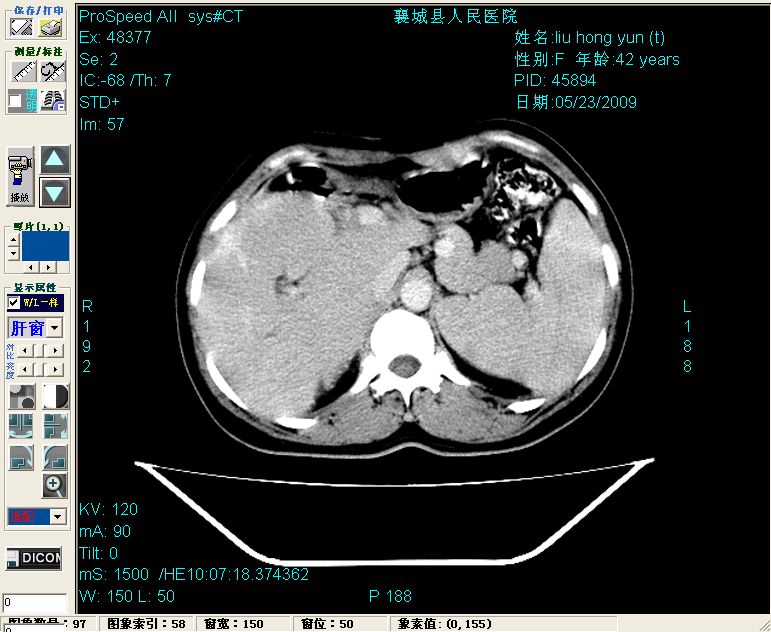

增强:

增强动脉期前述低密度区轻度早其强化,门脉期强化程度显著增高,延期扫描强化程度下降,但仍为相对高密度影

胰头部见结节状高密度影,其前方略可分辨扩强胆部管,平扫到增强始终有,但现在尚难与胃肠造影剂鉴别.

结合病史考虑,1现在引起黄疸体征的原因应该是胆总管胰段结石阻塞,建议局部胃肠造影剂排空后复查.

2左肝及右肝前叶表现考虑胆囊摘除术后所致的肝动门脉瘘形成,慢性纤维组织炎性增生.不完全除外左肝胆管细胞癌

3脾大,可能与动门脉瘘所致门脉高压有关

1)肝内胆管结石,胆总管末端结石伴肝内胆管扩张。2)肝左叶及肝右叶前段增强前后之异常表现,考虑炎性改变,不排除胆管细胞癌。

1)肝内胆管结石,胆总管末端结石伴肝内胆管扩张。2)肝左叶及肝右叶前段增强前后之异常表现,考虑炎性改变,不排除胆管细胞癌。3)脾大。